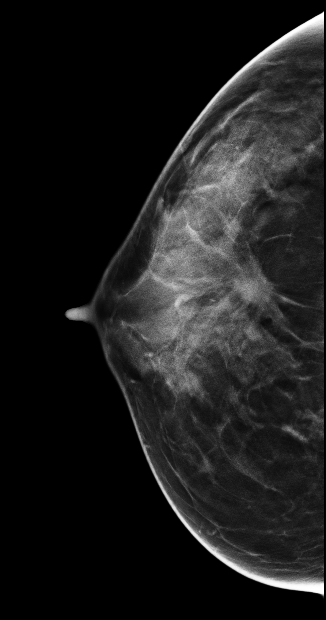

DBT图像:

影像描述: 在2DMLO位图像的上象限发现一不对称局限性致密影,但CC位上未见明显异常病变区域,在V-Preview图像上MLO位上病变显示明显逼2D更清晰,在CC位上乳头后方深部我们可以清晰的发现病灶,在3D-plane图像上我们可以更进一步清楚观察到病变形态大小范围,以及病灶边缘呈星芒样长短不一毛刺样改变。 影像诊断: 右乳偏外象限局限致密影,考虑BI-RADS 4B 。 病例点评: 病理证实右乳浸润性导管癌,DBT可以给我们提供更多诊断信息有助于明确病变性质。